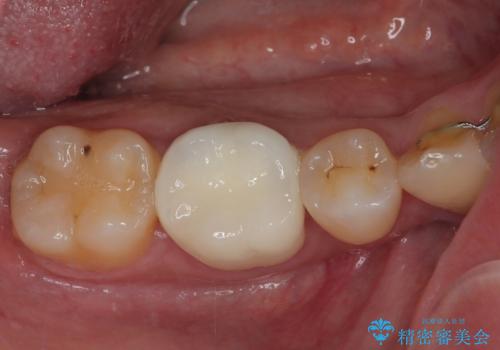

最新の症例

Latest cases